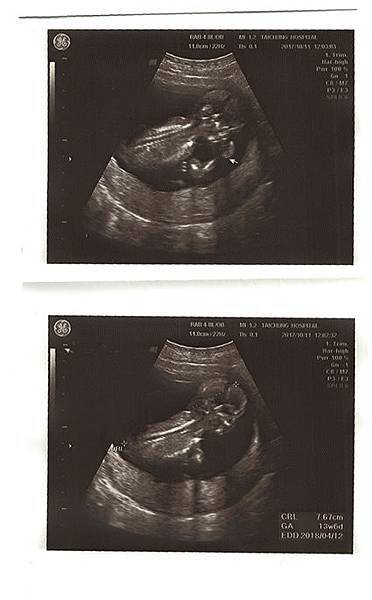

接著照超音波,這次直接照腹部超音波就看得清楚了,寶寶長大了,脊椎看得好清楚,雙手還揮來揮去的,太可愛了~!

醫生說他的姿勢像個小沙彌,在揮手、吃手~Chris在旁邊看了笑得好開心。

心跳147下,身高7.67cm,都在標準值喔!寶寶好棒~!

21W5D 到由劉醫師轉介的孕兒診所照高層次超音波,孕兒診所小小間的,但很溫馨,裡面很溫暖,大家也都非常親切~

我們早上10:10照到大概10:40,剛開始照的時候,寶寶就把雙手打開,乖乖的讓他們數手指,操作師說寶寶很棒,因為大部份寶寶都會手握拳頭~

照的很快也很詳細,聽到每個部分都ok的時候,真的放心許多!只是寶寶躺得很舒服,照不太到更詳細的脊椎,操作師跟在後面觀看螢幕的賴醫師一直跟寶寶說:弟弟啊~翻一下~轉一下~!

但寶寶始終躺的舒服,醫師請我們先出去外面吃個糖果,走一走~過十分鐘後再進去照,還是一樣的姿勢~於是醫師請我們40分鐘後再回來~

我和Chris就跑去逛附近的菜市場,買了一些菜,也在那邊吃了麵,一邊跟寶寶喊話。

結果40分鐘後回去,寶寶還是維持那個姿勢躺得好舒服阿,醫師跟我們說,有的人為了照那個部位,一共來了三次~因為需要寶寶趴著,這真的要看運氣啊。

只好再找時間回去一趟了~但聽到其他部位一切正常,真是好棒好棒的消息,而且賴醫師說:你們的寶寶營養特別好哦!

因為實際週數21W5D,照出來有23W3D,寶寶614g~醫師還要我少吃點甜的~噗~其實我不愛吃甜食,我想都是媽媽給的滴雞精很營養!

滿23W這天又到孕兒診所回診,要照上次沒有照得太清楚的腰椎跟劍椎的部分,一躺下來寶寶還是維持上次那個仰躺的舒服姿勢~

噗...看來前一天對寶寶的喊話沒有奏效,醫生要我出去吃個糖果再進去照一次,結果還是一樣......

只好再等40分鐘,這天因為Chris工作忙,他就先去處理工作的事了,我在外面的公園散步晃晃,和寶寶喊話,買飯卷跟養樂多填填肚子,看吃吃東西寶寶會不會換姿勢~

結果第三次進去,寶寶還是躺得舒服~醫生說寶寶很堅持哦!然後我即將成為他們診所第三位要來第三次的媽媽~

但賴醫師很好,他說基本上他看過是可以的~只是因為他們照得更加仔細一些,所以第三次我可以選擇要不要來~

我們想說下次約下午時間看看,再照一次~

23W5D產檢日,寶寶體重886g,醫生說一切都很標準,寶寶似乎大了兩週呢!

這次的4D照好清楚喔!鼻子、嘴巴長得超像Chris!!連醫生都說比較像爸爸~呵呵

而且寶寶這次胎位轉正囉!!關於陰部疼痛的問題,我再次問了劉醫師,劉醫師說如果有點腫腫的,應該是靜脈曲張,開了一條凝膠給我擦在會疼痛的地方~